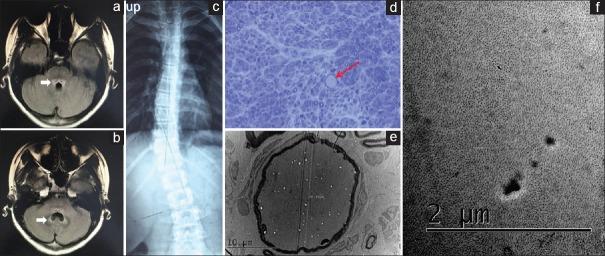

Giant Axonal Neuropathy with Unusual Neuroimagings Caused by Compound Heterozygous Mutations in GAN Gene.

https://cdn.ncbi.nlm.nih.gov/pmc/blobs/aca8/6166460/8b801b39e355/CMJ-131-2371-g001.jpg